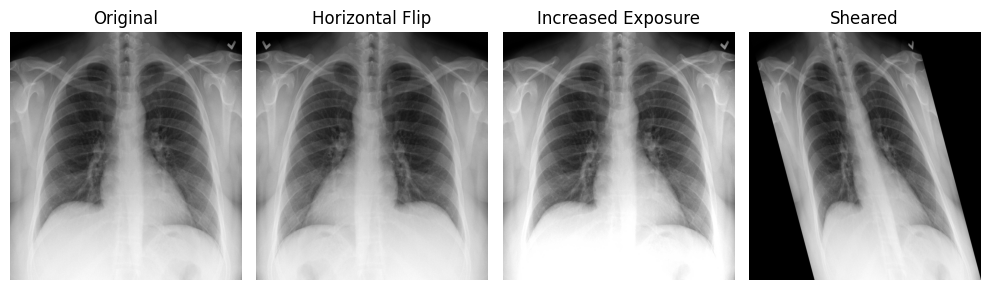

Data augmentation is the process of generating additional training samples by transforming existing images. Numerous studies show that it improves model performance on independent, unseen data, and it is now a standard practice in medical AI development. [1]

According to [2], commonly used augmentation techniques fall into two main groups:

Classical augmentations

- Rotation

- Flipping (mirroring)

- Translation: shifting the image along one or more axes

- Scaling: zooming in or out

- Shearing: sliding one image edge while keeping the opposite edge fixed

- Intensity augmentation: modifying pixel values (e.g., blurring, sharpening, brightness/contrast adjustments, histogram equalization, normalization)